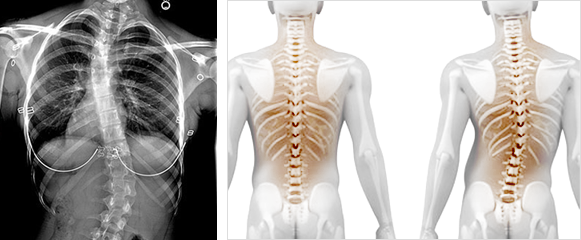

척추가 좌우로 휘어지는 척추 변형으로 골반이나 어깨의 높이가 다르거나

몸통이 한쪽으로 치우쳐 보이는 것이 특징인 허리질환입니다.

척추측만증은 성장기 소아 청소년들에게 많이 발생하며,

척추가 옆으로(대부분 우리나라 청소년은 S형으로 휘어짐)

휘어지는 것을 말합니다.

한번 휘어진 척추는 성장기 동안 키가 크는 과정에서

그 각도가 점점 심해지게 되는데

발병 초기에 정확히 검진하여 30~40도 이상의 악성 측만증으로

휘어지는 변형을 막는데 초점을 맞추어야 합니다.

01. 피검자는 신발을 벗고 두발을 모아섭니다.

02. 피검자는 무릎을 편 상태로 허리를 굽힙니다.

03. 검사자는 피검자 뒤에서 양쪽 어깨의 높이를 비교합니다.

04. 어깨 높이의 차이를 보인다면 척추측만증을 의심해봐야 합니다.

05. 10도 이상 측만각을 보인다면 척추측만증으로 진단할 수 있습니다.

※ 각도의 정도에 따라 치료의 방법도 달라지고 환자의 나이에 따라서도

영향이 있기 때문에 단순히 자가 진단만으로 한계가 분명히 있으며,

해당 증상이 감지되면 엑스레이 촬영 등 정확한 검진을 꼭 받아보시기 바랍니다.